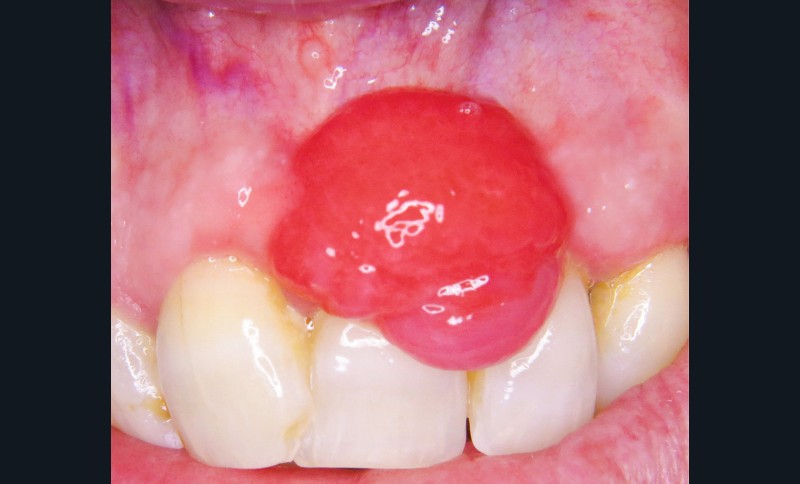

1. Épulis inflammatoire (plasmocytaire)

- Nodule indolore, pédiculé, érythémateux, parfois ulcéré (fig. 1a).